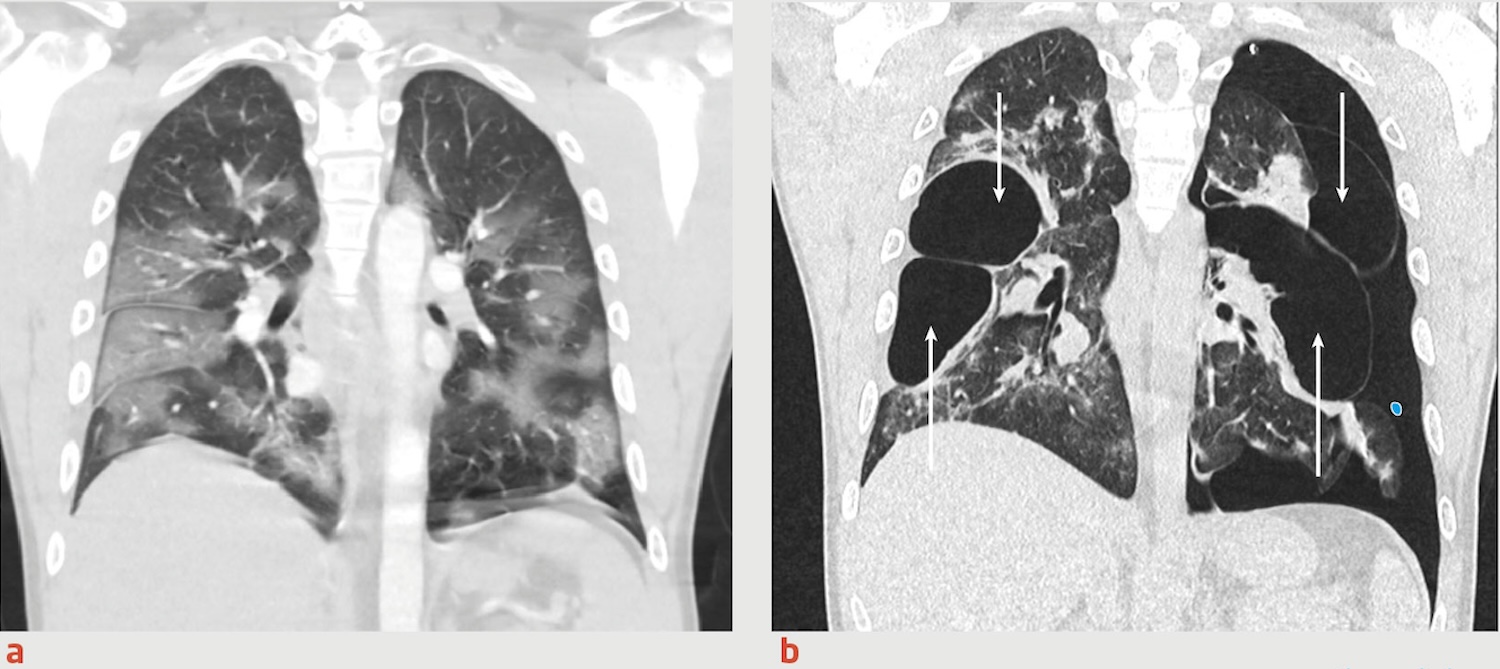

Daar onderging ze geavanceerde hersenscans die volgens Amerikaanse artsen kleine ontstekingen en weefselveranderingen lieten zien. Voor Dzambo voelde dat als een bevestiging dat haar klachten niet tussen de oren zaten. Ze stuurde haar bevindingen naar haar artsen in Nederland, maar kreeg naar eigen zeggen geen reactie. “Ik wilde alleen serieus genomen worden,” vertelde ze in een interview.

In een kliniek in Brabant werd op haar hersenscan een afwijkend patroon gezien dat volgens haar arts “ongebruikelijk” was voor haar leeftijd. Toch konden de specialisten niet met zekerheid vaststellen of dit door vaccinatie kwam. De Boer besloot zich verder te verdiepen in internationale onderzoeken en kwam in contact met buitenlandse experts.